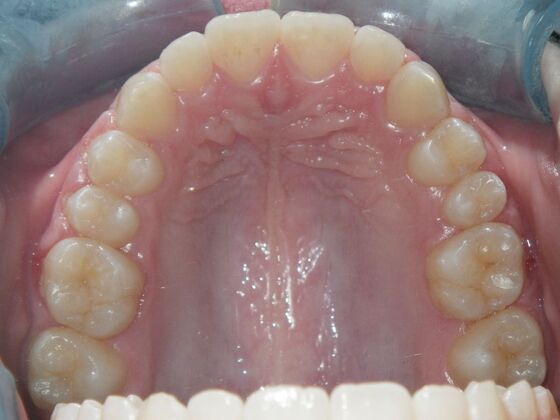

Orthodontics: Case 2

Description

Patient is 9 years old and presents with 100% overbite and blocked out upper and lower lateral incisors. Both upper central incisors are palatally inclined causing a lack of space available for most anterior teeth. Advised her parents that she needs Phase I Interceptive Orthodontic treatment to provide room for all upper and lower front teeth. Phase I treatment was begun and finished, then began Phase II treatment shortly thereafter to finalize case. Removable retainer were fabricated for retention.